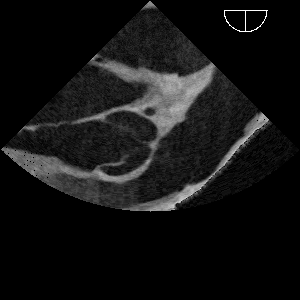

Jego podstawę stanowi opracowany w ramach wcześniejszych projektów, unikalny, objęty ochroną patentową symulator do przezprzełykowych badań echokardiograficznych.

Mamy nadzieję, że siłą wszystkich konsorcjantów – inżynierów z Akademii Górniczo-Hutniczej, we współpracy z ośrodkami klinicznymi prowadzącymi projekty telemedyczne, grupą bardzo doświadczonych nauczycieli akademickich, od lat zajmujących się nauczaniem echokardiografii, zespołem profesora Nowińskiego wnoszącego swoje światowe doświadczenie w opracowywaniu trójwymiarowych atlasów anatomicznych, powstanie unikalne dzieło – zintegrowany system sprzężonych (mistrz-uczeń i mistrz-klasa) symulatorów do echokardiografii przezklatkowej i przezprzełykowej, wspartych trójwymiarowym Atlasem Anatomii Serca, umożliwiających szkolenia na odległość.